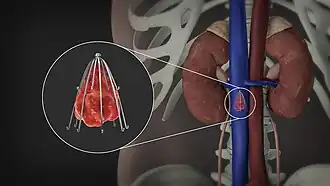

3D Medical Animation still shot showing the Inferior vena cava filter

Inferior vena cava filter - Gunther Tulip.[1]

An inferior vena cava filter is a medical device made of metal that is implanted by vascular surgeons or interventional radiologists into the inferior vena cava to prevent a life-threatening pulmonary embolism (PE) or venous thromboembolism (VTE).[2][3]

The filter is designed to trap a blood clot and prevent its travel to the lung where it would form a pulmonary embolism.[4][3] Their effectiveness and safety profile is well established, and they may be used when anticoagulant treatment is not sufficient.[5]